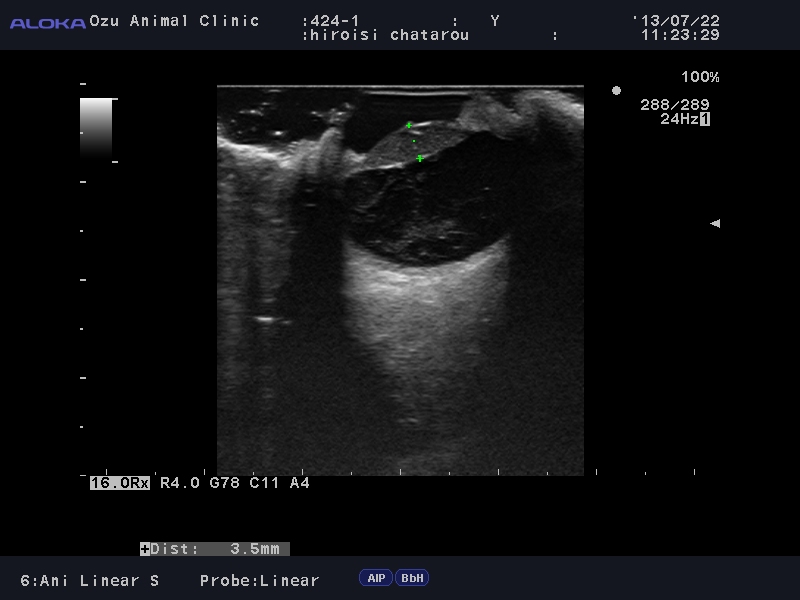

超音波検査:水晶体が完全に白濁している。